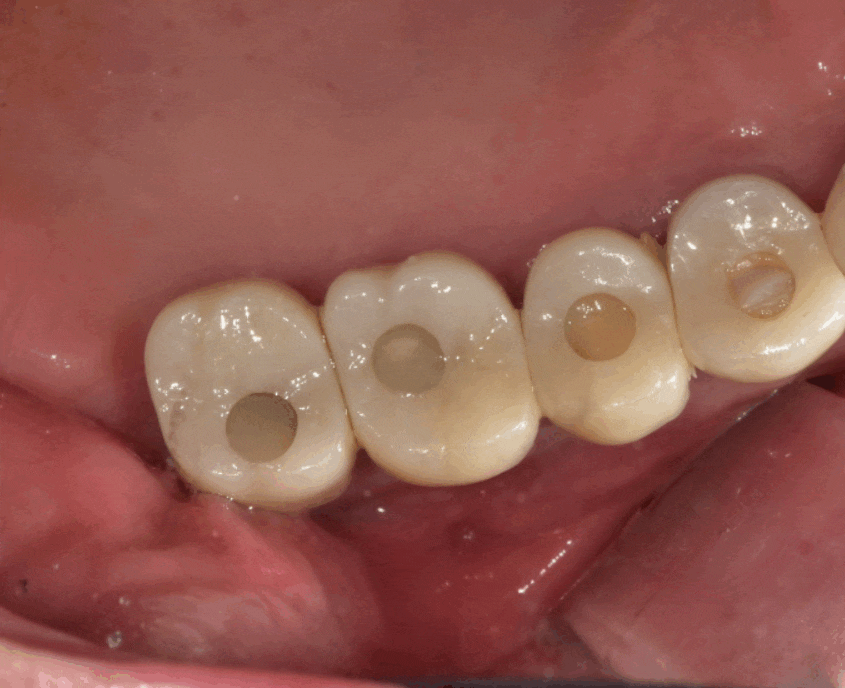

이제는 취급을 잘 안하는

은니를 사용해 씌운 치아입니다.

세월의 흔적을 보여주는 증거네요~

치아에 충치도 있고

잇몸 뼈도 녹아 흔들리고

예후를 생각하여 씌운 치아 뽑아서

고덕동 임플란트로 교체하는 것으로

상담해드렸습니다.

23.03.22

고덕동 치과 최대한 자연치아를 살리려 하기에..

뽑아야할 것 같았어도

보철부터 제거하여 안쪽 상태를 보았는데요.

치아 구멍이 뻥 뚫릴정도로

많이 썩고 삭았습니다.

이것은 못살리겠네요..

씌운 치아 벗겨 내고

상태 보고 뽑았습니다.

24.01.22

고덕동 치과치료 트렌드 따라 가야겠죠?

예전에는 은니로 많이 치료했지만

하얗고 단단한 지르코니아로~!

색깔도 맞춰서 마무리 해드렸습니다.